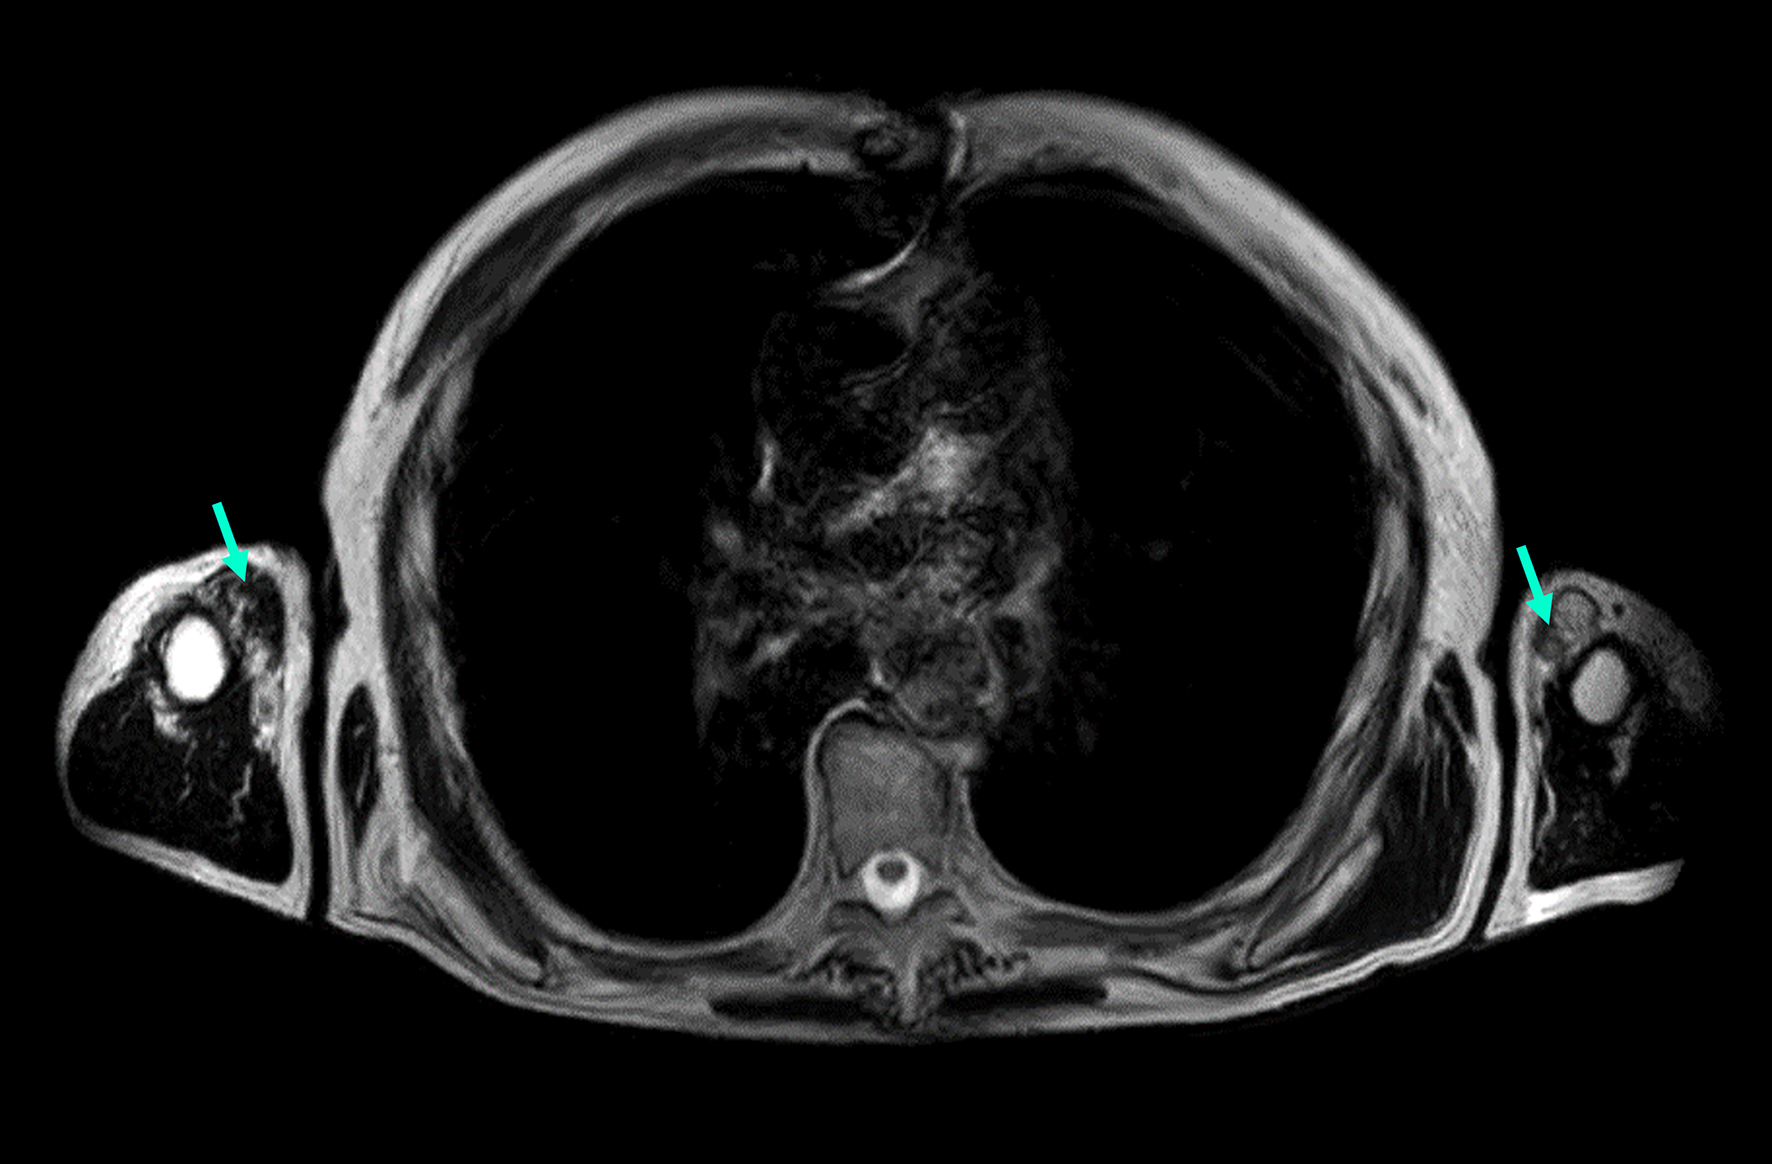

Individual 12 (currently in mid-70s) had a slowly progressive distal myopathy with disease onset in the fifth decade. On the last neurological examination, the patient had both waddling and steppage gait bilaterally

Figure 3. MRI image of an Individual 12 exhibiting proximal upper limb muscle involvement (axial T1-weighted images). The image demonstrates Mercuri grade IV fatty infiltration in the biceps (green arrows).

One patient (Individual 12) in our cohort exhibited upper body involvement and weakness, a condition that has been documented in one Finnish AD TMD patient (unpublished). The reason for this patient's arm involvement remains unclear, but it may be attributed to another alteration in the TTN gene or a different gene altogether. To date, only one VUS variant has been identified (NM_001267550.2(TTN):c.73994C>T, p.(Thr24665Met), which has an unclear impact on the atypical phenotype [Supplementary Table 1].